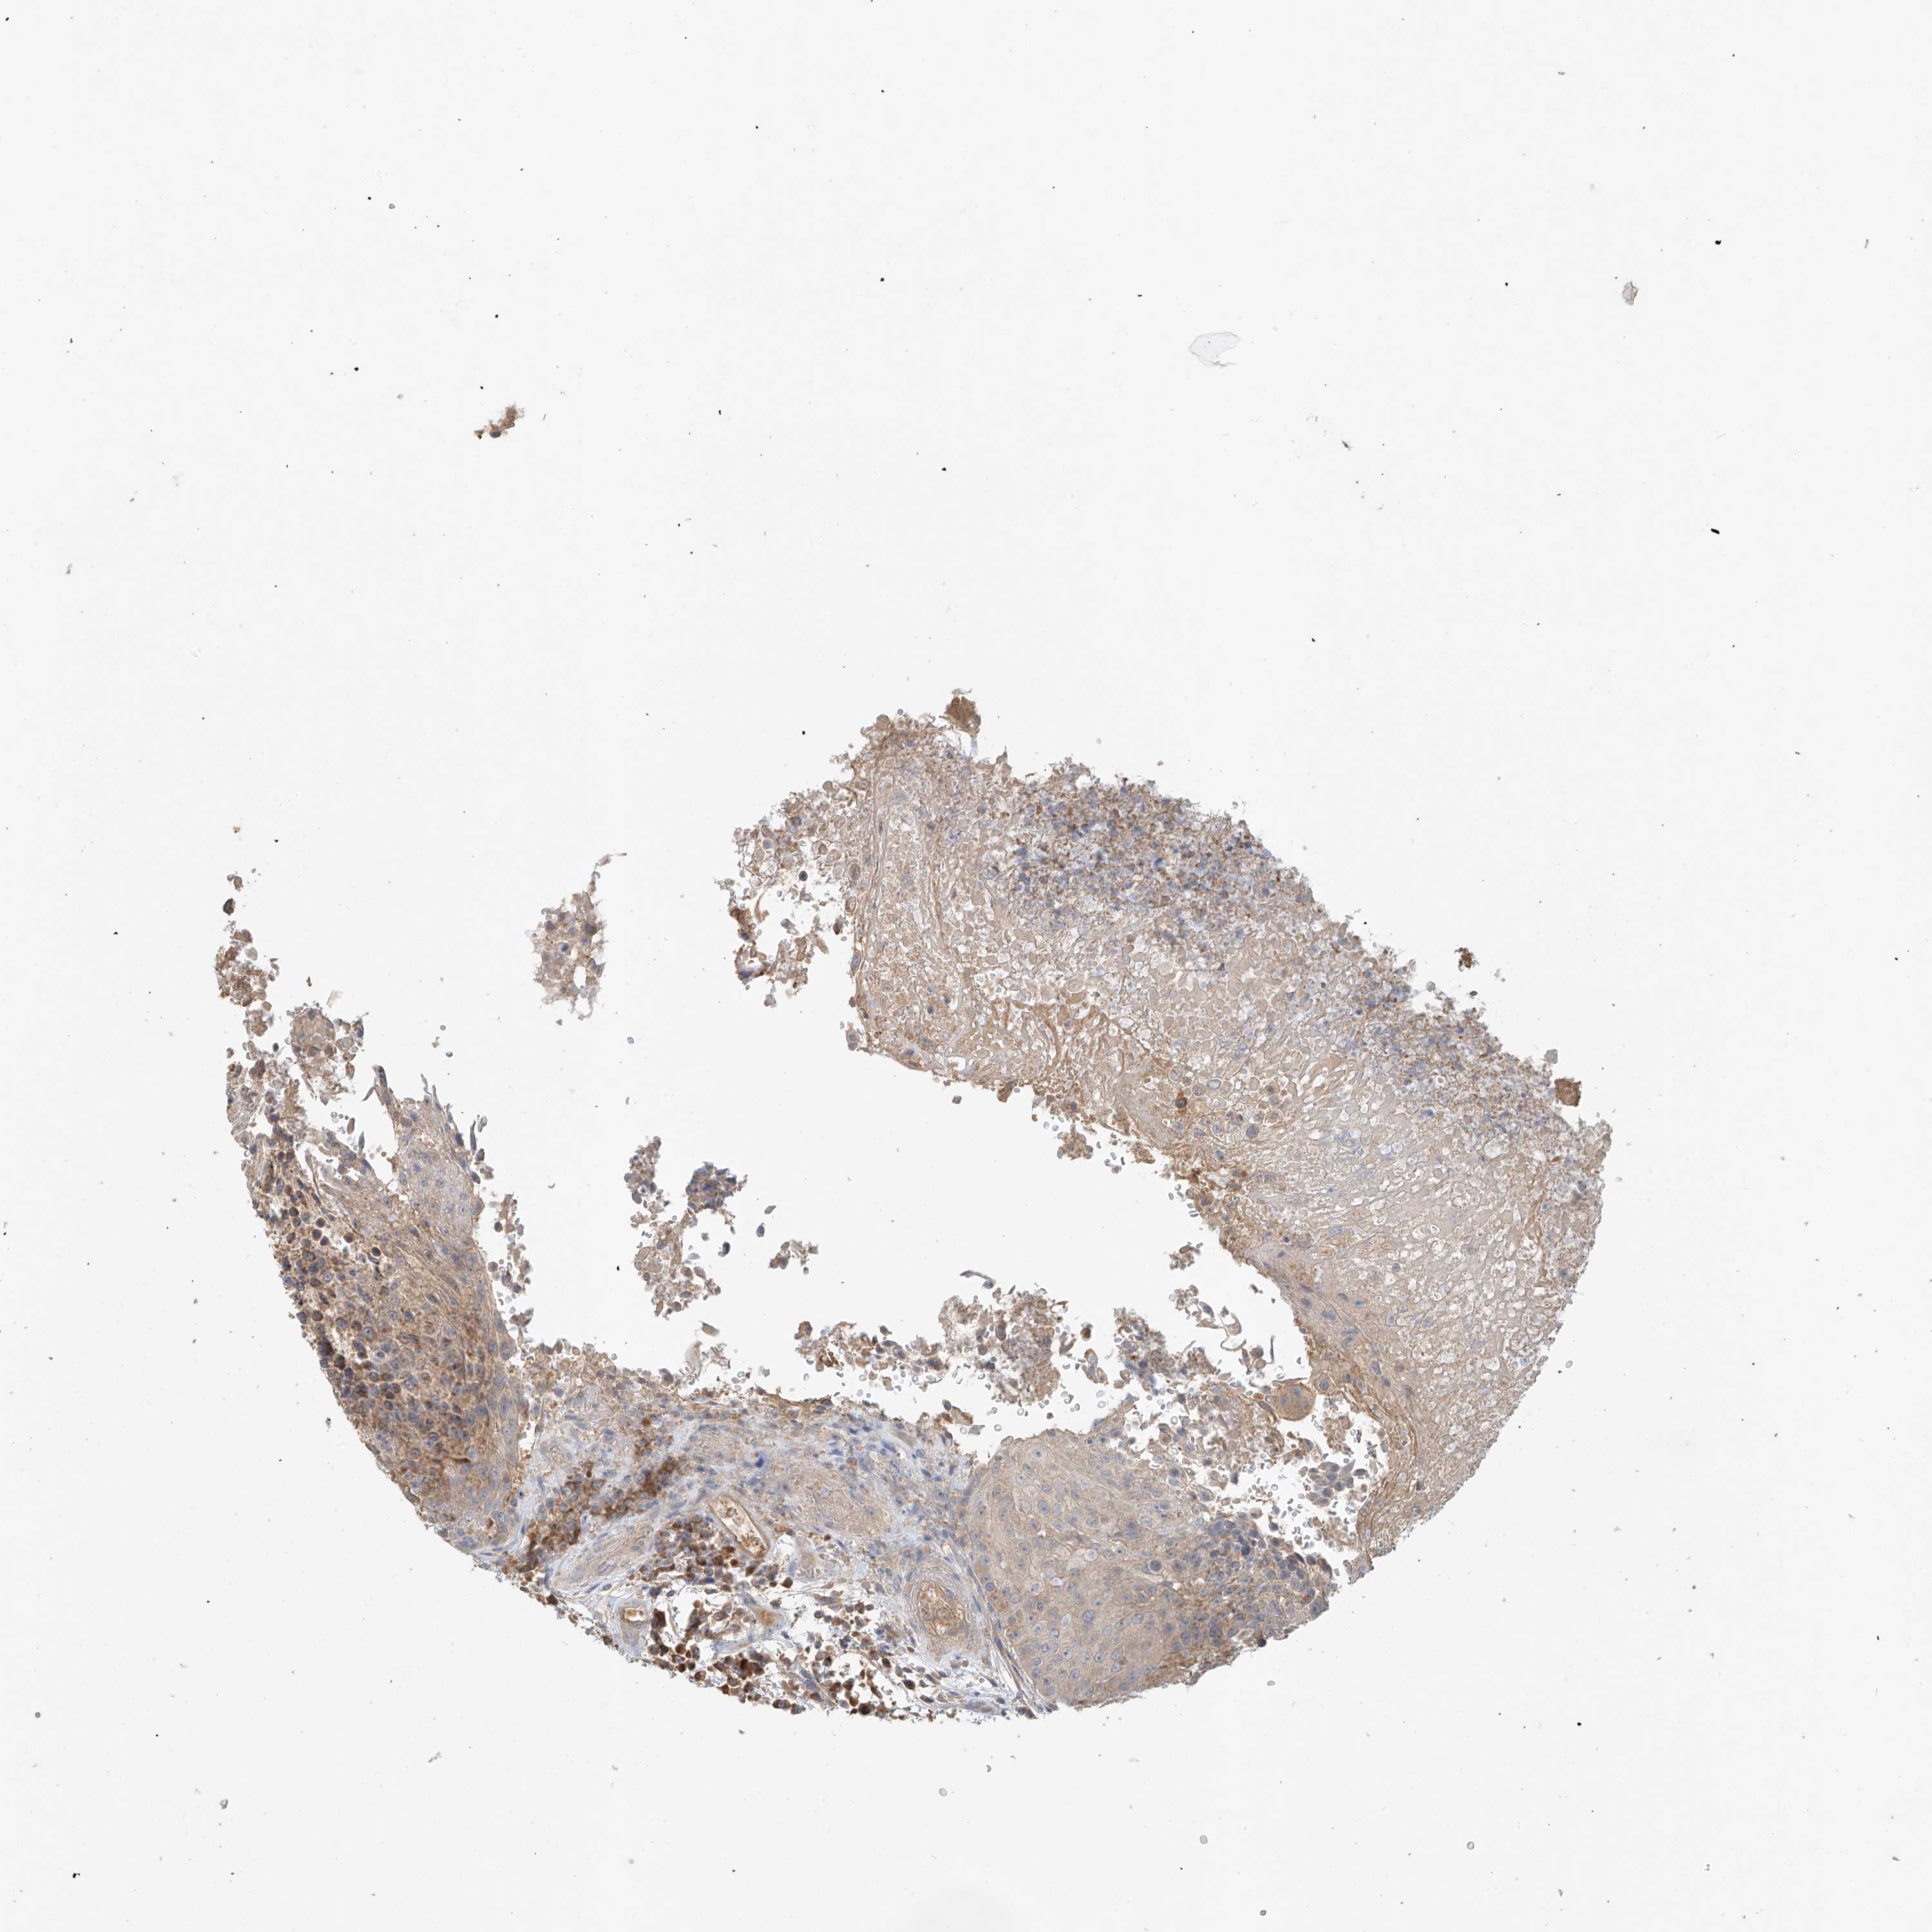

UROTHELIAL CANCER - Protein expressioni

A mouse-over function shows sample information and annotation data. Click on an image to view it in a full screen mode. Samples can be filtered based on level of antibody staining by selecting one or several of the following categories: high, medium, low and not detected. The assay and annotation is described here.

Antibody stainingi

Antibody staining in the annotated cell types in the current human tissue is reported as not detected, low, medium, or high, based on conventional immunohistochemistry profiling in selected tissues. This score is based on the combination of the staining intensity and fraction of stained cells.

Each image is clickable and will lead to virtual microscopy that enables deeper exploration of all samples and also displays staining intensity scores, fraction scores and subcellular localization as well as patient and tissue information for each sample.

Antibody HPA034627

Staining

High

Medium

Low

Not detected

Intensity

Strong

Moderate

Weak

Negative

Quantity

>75%

75%-25%

<25%

None

Location

Nuclear

Cytoplasmic/membranous

Cytoplasmic/membranous,nuclear

Urothelial carcinoma, Low grade

Urothelial carcinoma, High grade